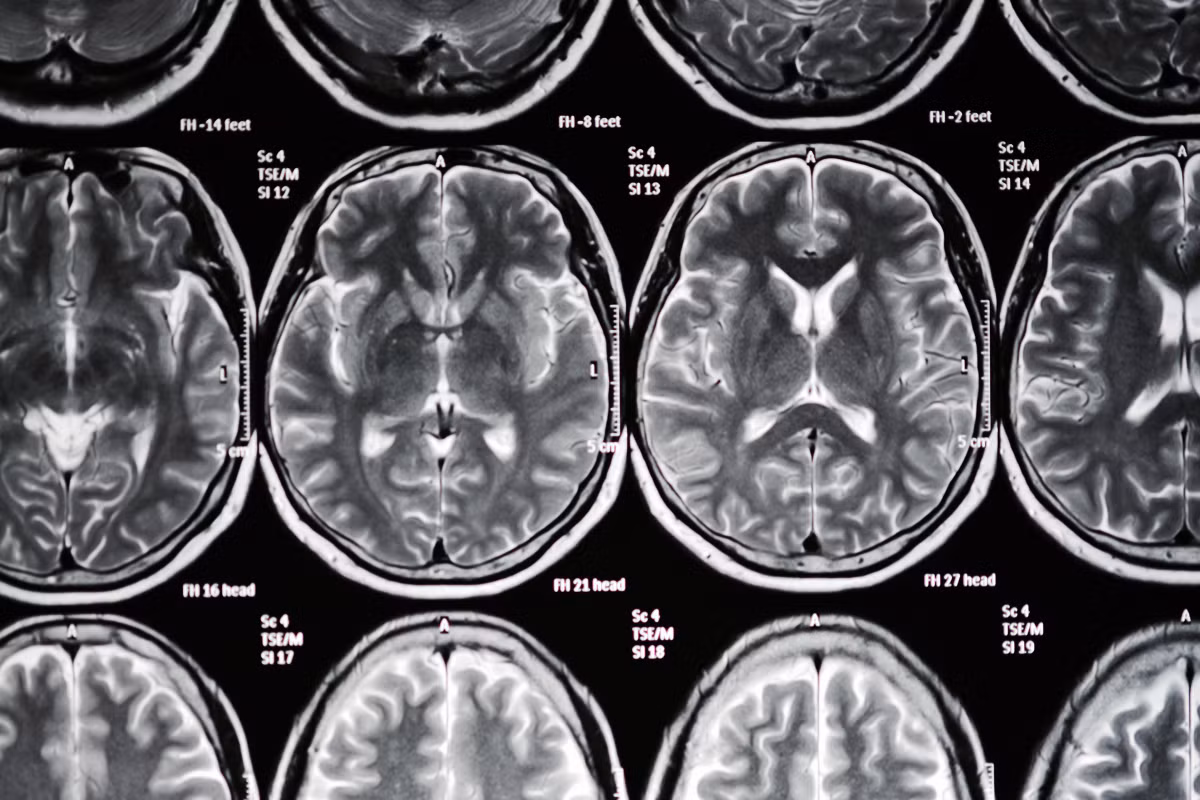

(Kiến Thức) - Nguy cơ đột quỵ càng tăng cao ở những phụ nữ sử dụng thuốc tránh thai, sử dụng thuốc lá, hay người đang mang thai. Do đó, chúng ta cần nắm được những dấu hiệu đột quỵ ở phụ nữ để cấp cứu kịp thời.

Hầu hết mọi người thường cho rằng đột quỵ chỉ xuất hiện khi tuổi già ập đến. Tuy nhiên, trong thực tế, tỷ lệ phụ nữ trẻ bị đột quỵ đang ngày càng gia tăng. Tất cả các cơn đột quỵ đều cần điều trị càng sớm càng tốt. Sau đây là dấu hiệu đột quỵ ở nữ giới và tất cả các lứa tuổi.

Bị co giật: Đột quỵ rất nguy hiểm vì chúng có thể nhanh chóng gây tổn thương não - và co giật có thể là một dấu hiệu của tổn thương não. Nếu bạn bị cơn co giật đột ngột, hãy đến bệnh viện ngay lập tức.